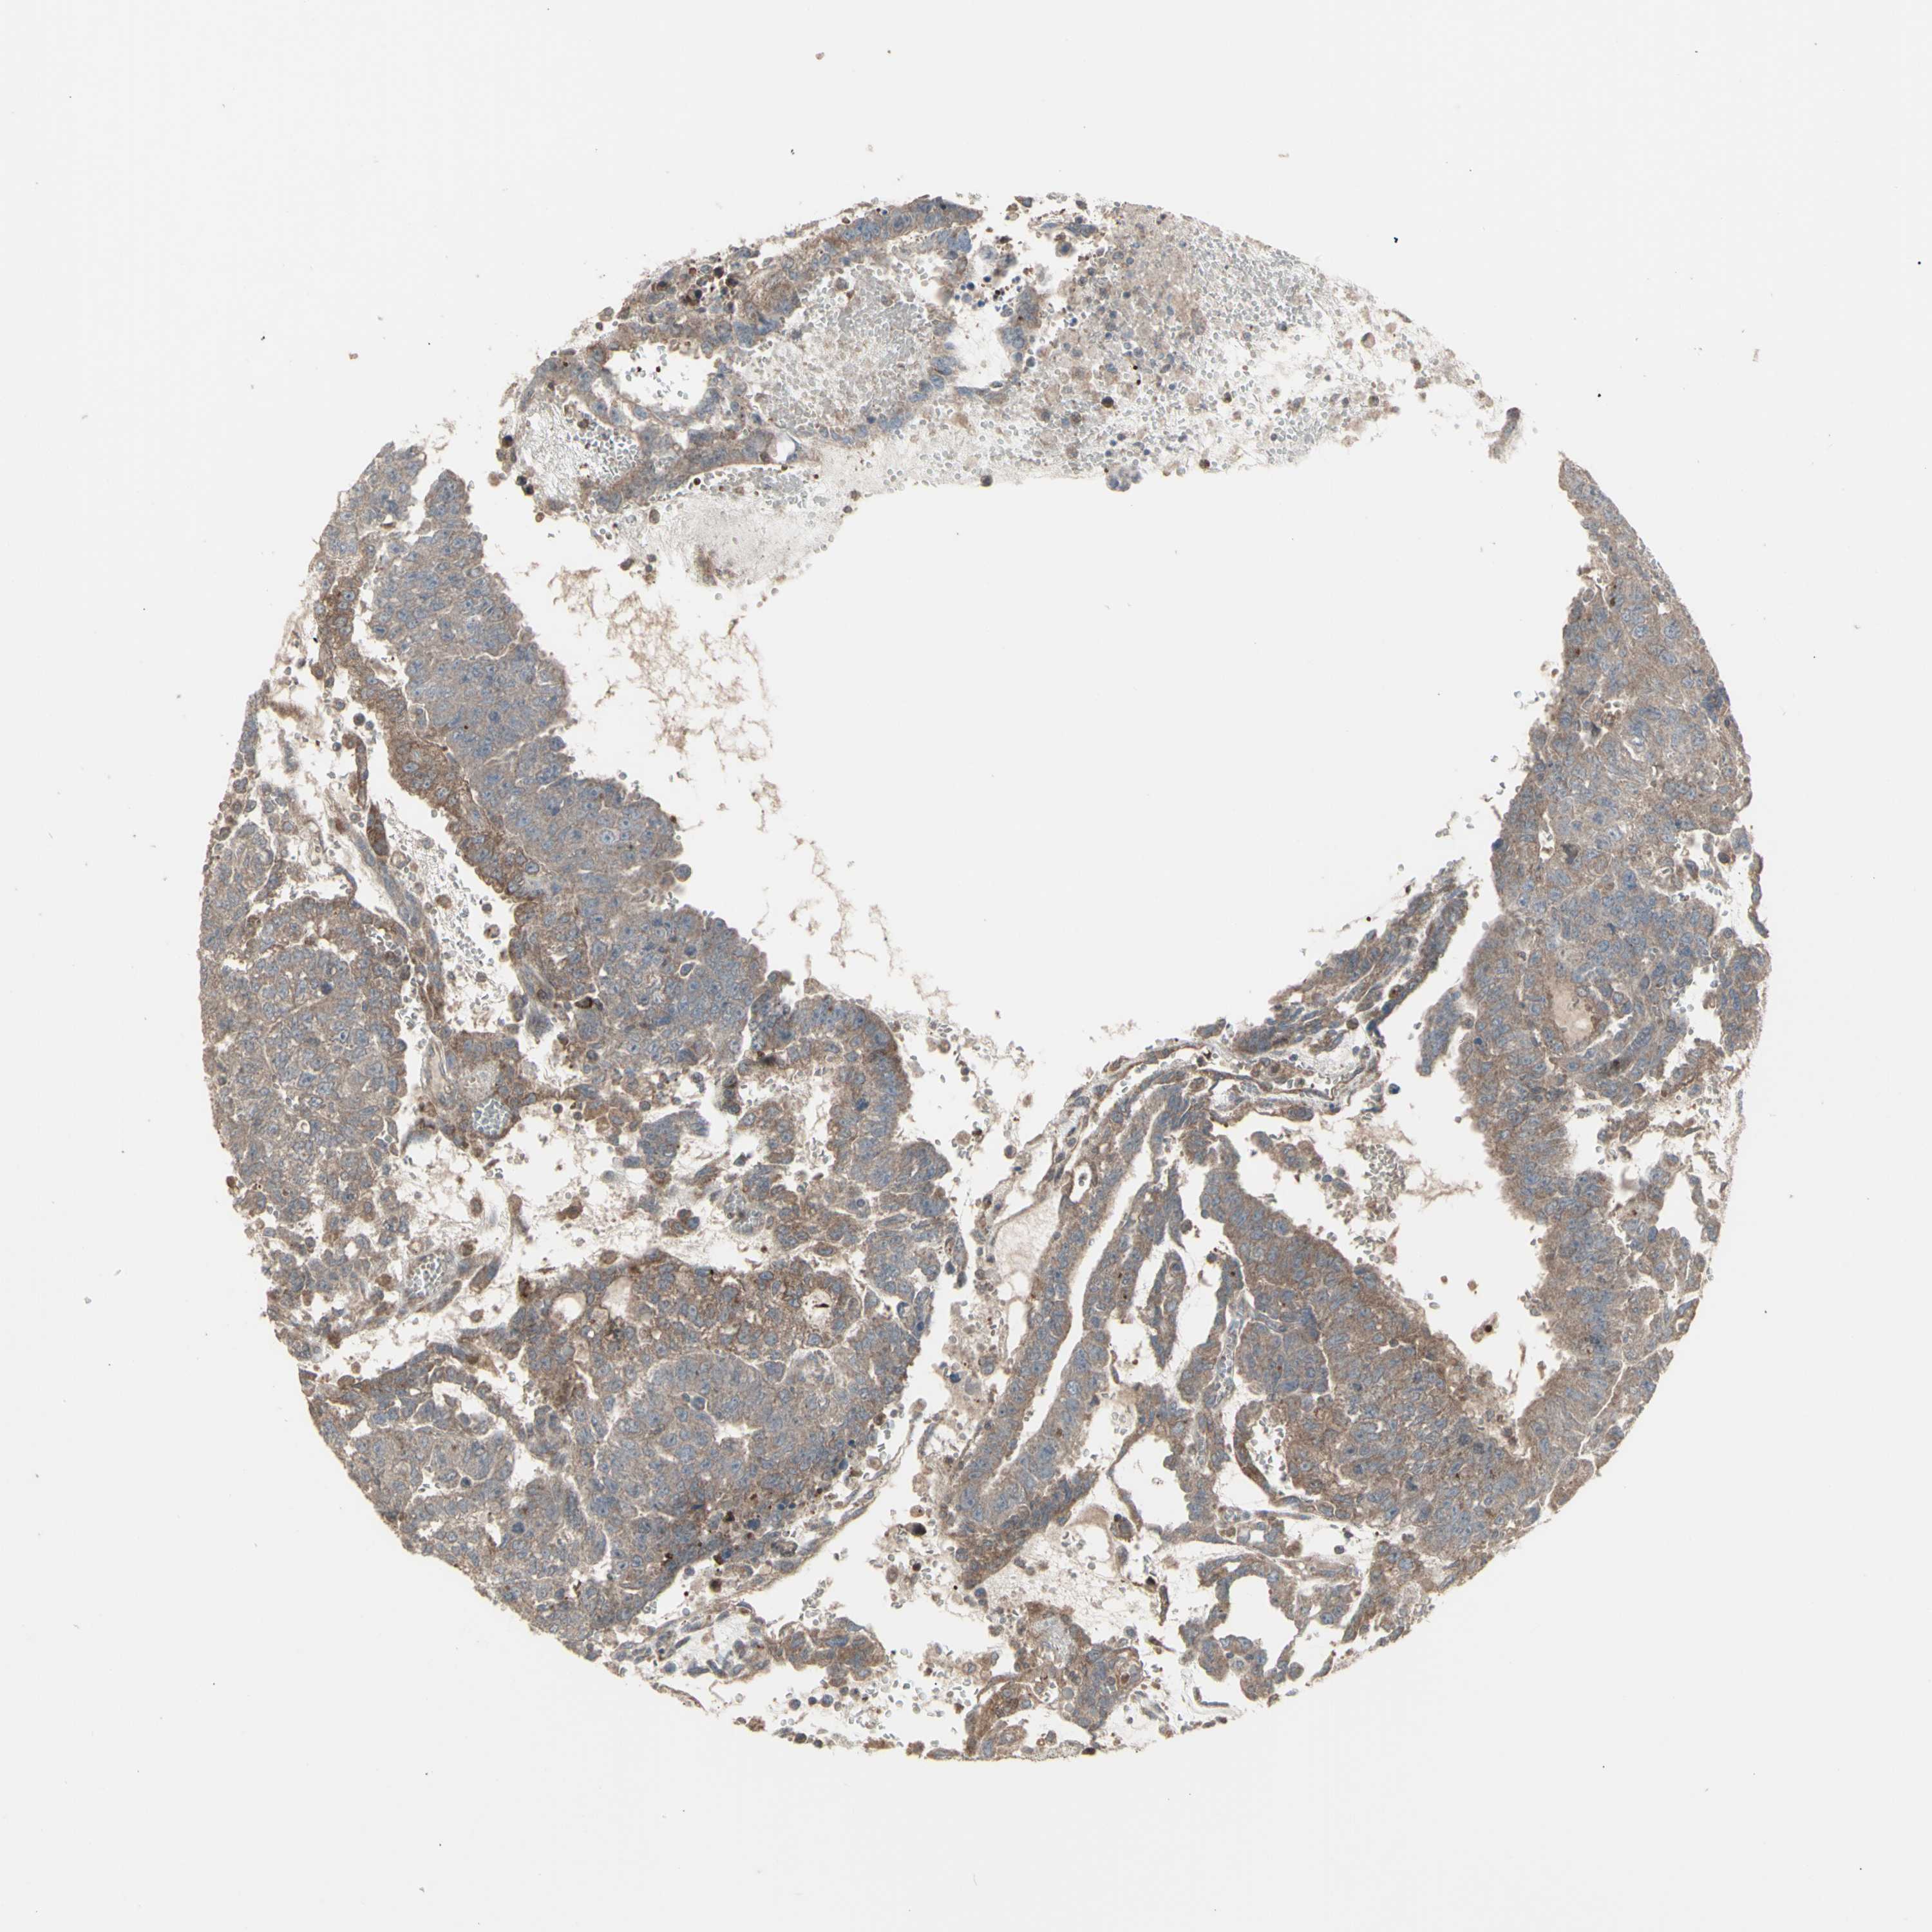

TESTIS CANCER - Protein expressioni

A mouse-over function shows sample information and annotation data. Click on an image to view it in a full screen mode. Samples can be filtered based on level of antibody staining by selecting one or several of the following categories: high, medium, low and not detected. The assay and annotation is described here.

Note that samples used for immunohistochemistry by the Human Protein Atlas do not correspond to samples in the TCGA dataset.

Antibody stainingi

Antibody staining in the annotated cell types in the current human tissue is reported as not detected, low, medium, or high, based on conventional immunohistochemistry profiling in selected tissues. This score is based on the combination of the staining intensity and fraction of stained cells.

Each image is clickable and will lead to virtual microscopy that enables deeper exploration of all samples and also displays staining intensity scores, fraction scores and subcellular localization as well as patient and tissue information for each sample.

Antibody HPA002633

Antibody CAB010906

Seminoma, NOS

Carcinoma, Embryonal, NOS